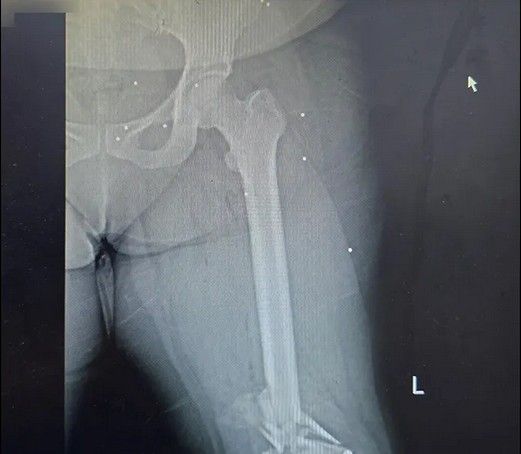

دست و پای معترضان در شهر رشت نیز از شلیکهای ماموران جمهوری اسلامی در امان نبودهاند. تصاویر رادیوگرافی نشان میدهد بسیاری از معترضان در ناحیه دست و پا هدف تیرهای ساچمهای قرار گرفتهاند، شدت آسیب در برخی موارد تا حدی بوده که استخوان ساعد، ساق یا مچ پا خرد شدهاند. همچنین موارد متعددی از شکستگی در دست و پای معترضان بدون شلیک گلوله نیز دیده میشود.

یکی از شدیدترین جراحات متعلق به زنی است که نه تنها کتف، بازو، ران و ناحیه تناسلی او هدف تیر ساچمهای قرار گرفته است، بلکه استخوان ران او نیز با اصابت گلوله جنگی خرد شده است. در تصاویر مشخص است که از فیکساتور برای درمان این مجروح استفاده شده است.

استخوانهای خردشده دست و پادست و پای معترضان در شهر رشت نیز از شلیکهای ماموران جمهوری اسلامی در امان نبودهاند. تصاویر رادیوگرافی نشان میدهد بسیاری از معترضان در ناحیه دست و پا هدف تیرهای ساچمهای قرار گرفتهاند، شدت آسیب در برخی موارد تا حدی بوده که استخوان ساعد، ساق یا مچ پا خرد شدهاند. همچنین موارد متعددی از شکستگی در دست و پای معترضان بدون شلیک گلوله نیز دیده میشود.